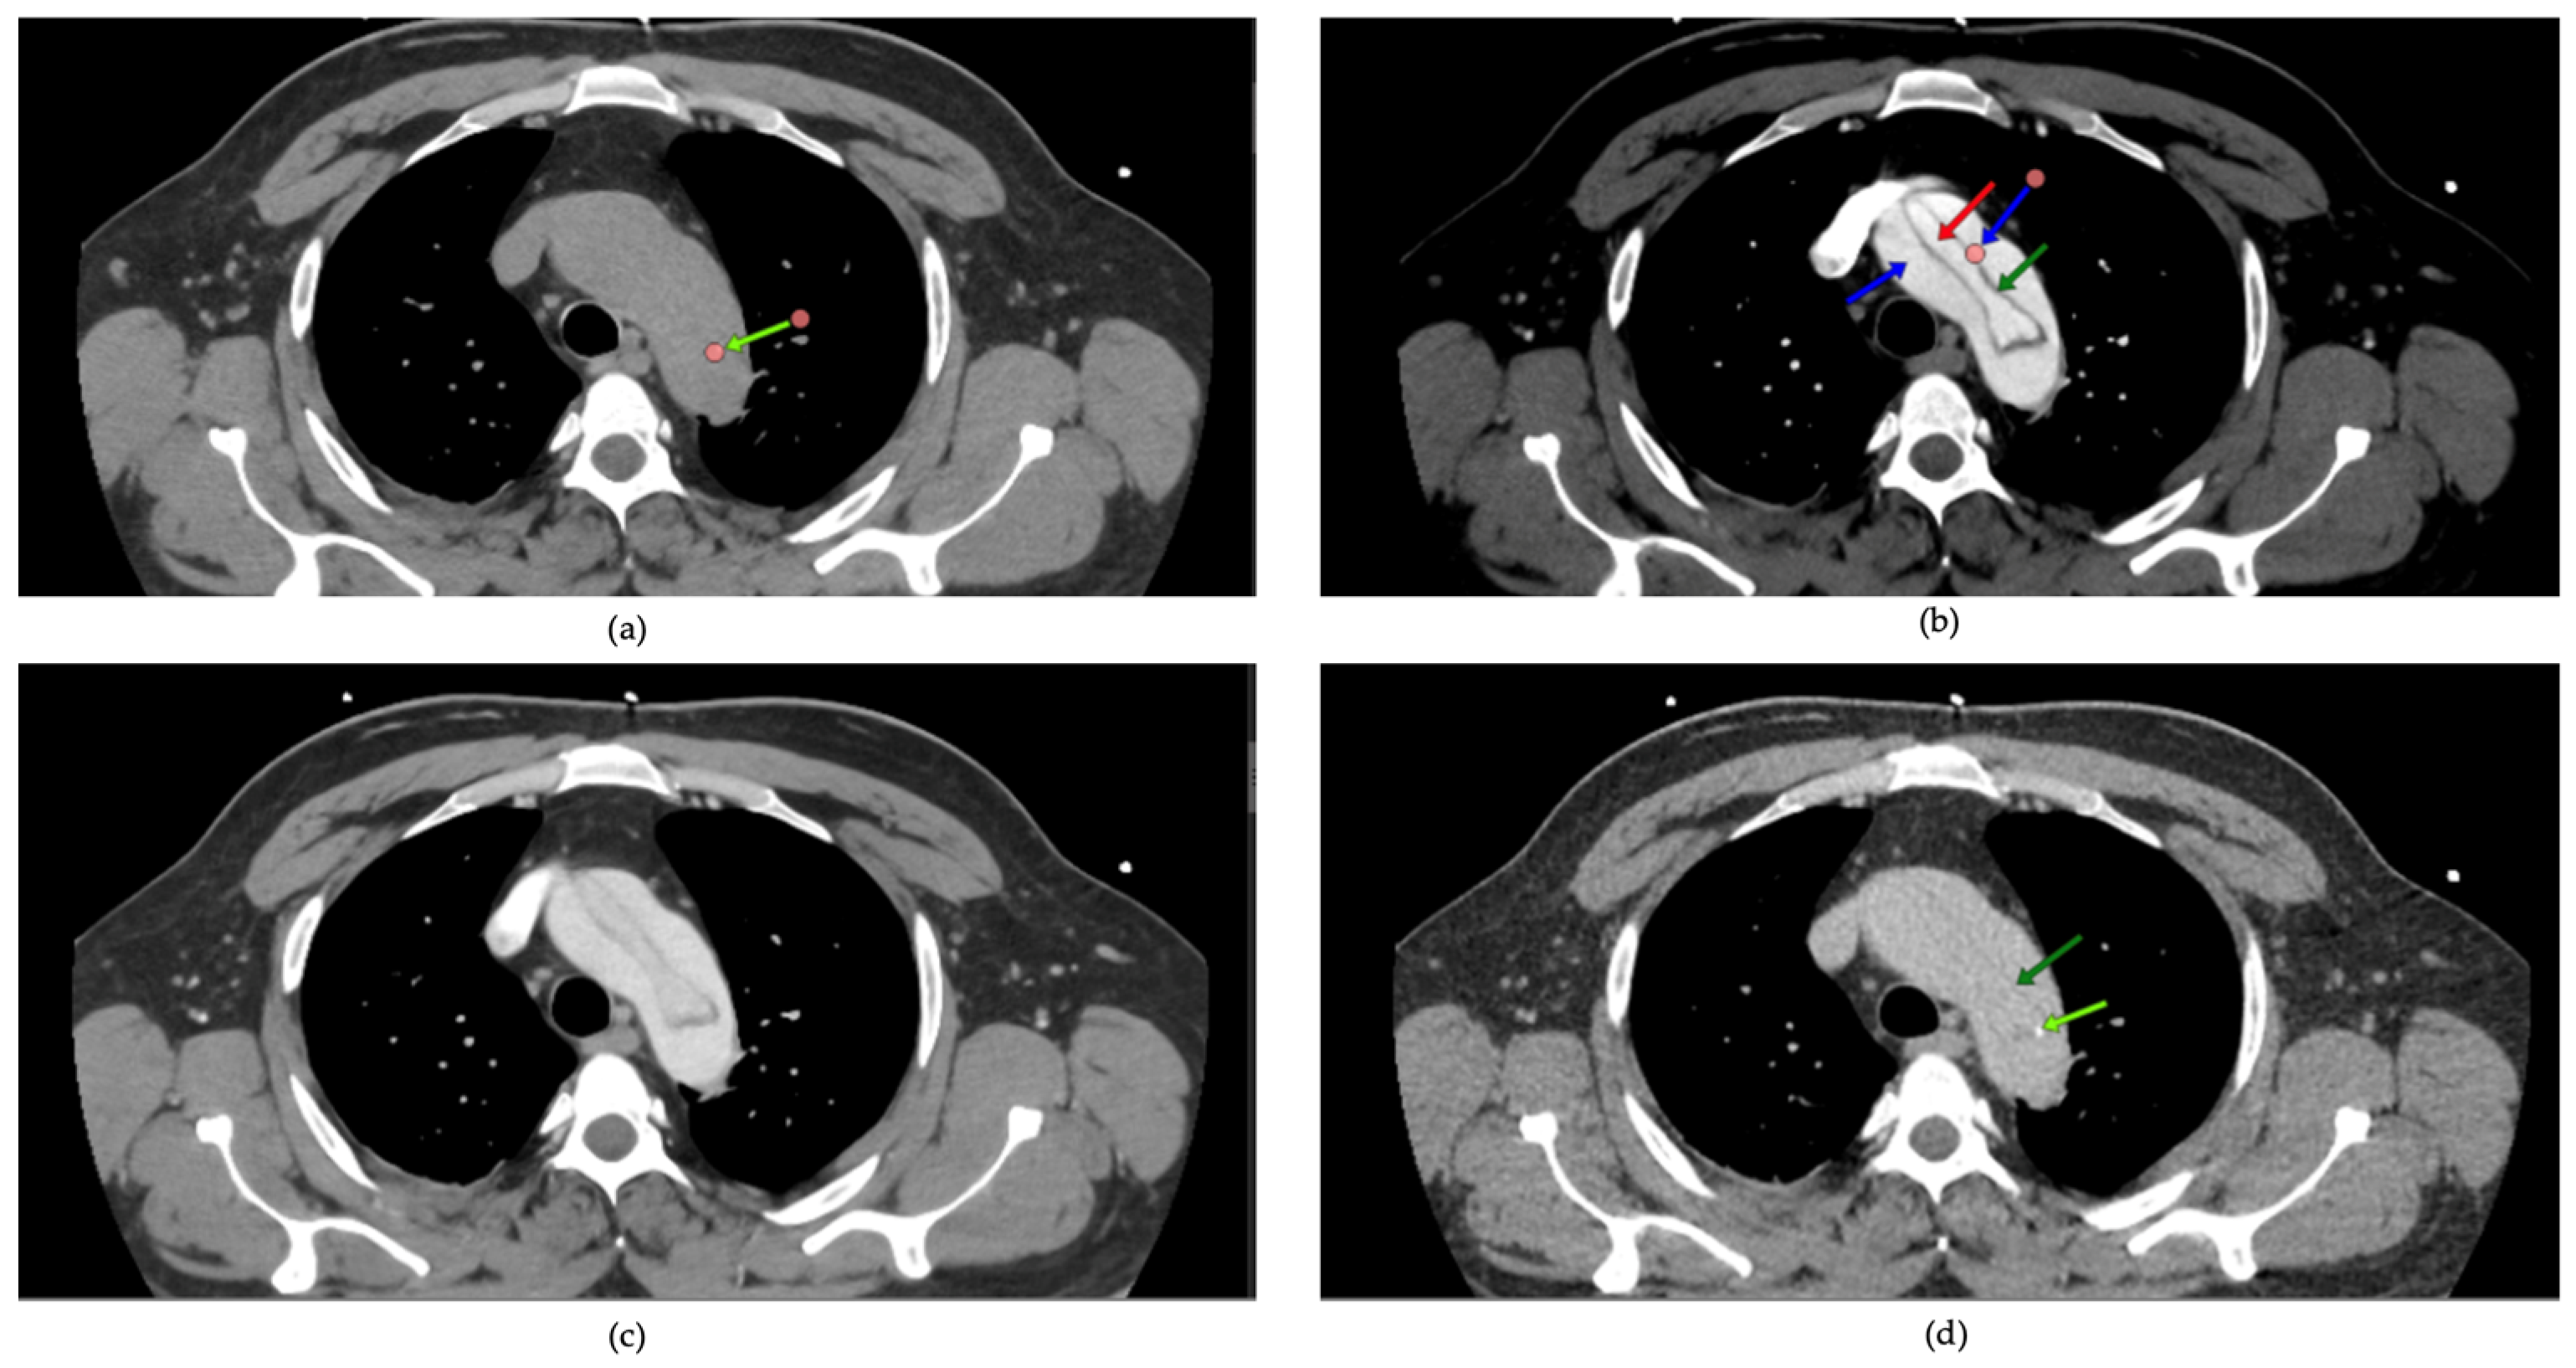

CTA indicated that all cases were associated with Stanford Type A dissections. In 23.1% of patients, dissection extended to the aortic arch, whereas 38.5% exhibited involvement of the descending aorta. Echocardiography results revealed that 26.9% of patients exhibited moderate to severe aortic regurgitation, while 19.2% showed pericardial effusion, thereby heightening the necessity for surgical intervention. The mean LVEF was 56.7%, suggesting that cardiac function was preserved in the majority of patients prior to surgery. Radiological evaluation of Stanford Type A aortic dissections provides essential insights into the pathophysiology and anatomy of the condition. Axial CT sections are particularly valuable in delineating the true and false lumens, as well as the intimal flap that separates them. Figure 5 highlights these features, demonstrating the compressed true lumen and the delayed opacification of the false lumen in the venous phase compared to the arterial phase. Additional findings, such as intimal calcifications, further contribute to a comprehensive understanding of the imaging characteristics of this pathology.

Figure 5. Multiphase CT imaging of Stanford Type A aortic dissection: true and false lumen analysis; (ad): axial CT images demonstrating characteristic findings of Stanford type A aortic dissection. Dark green arrow: intimal flap, marking the division between the true and false lumen; red arrow: true aortic lumen, compressed and reduced in size due to the higher pressure within the false lumen; blue arrow: false aortic lumen, which surrounds the true lumen and shows delayed opacification (arterial phase visible (b) versus venous phase in (c)); light green arrow: intimal calcifications within the aortic wall.